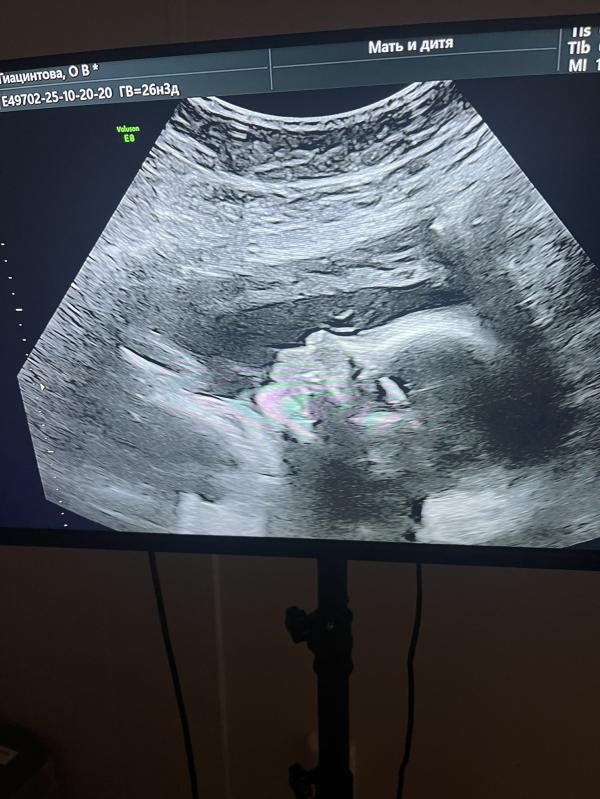

Человек в животе заставляет поволноваться, вчера активна была с сегодня опять никак, поехали в мать и дитя а дочь крутится, не дает узи сделать нормально 😍😌 сказали высокая будет, ножка уже большая)) активная очень, все хорошо в общем, живая) может я плохо ощущаю иногда ее из-за лишнего веса?